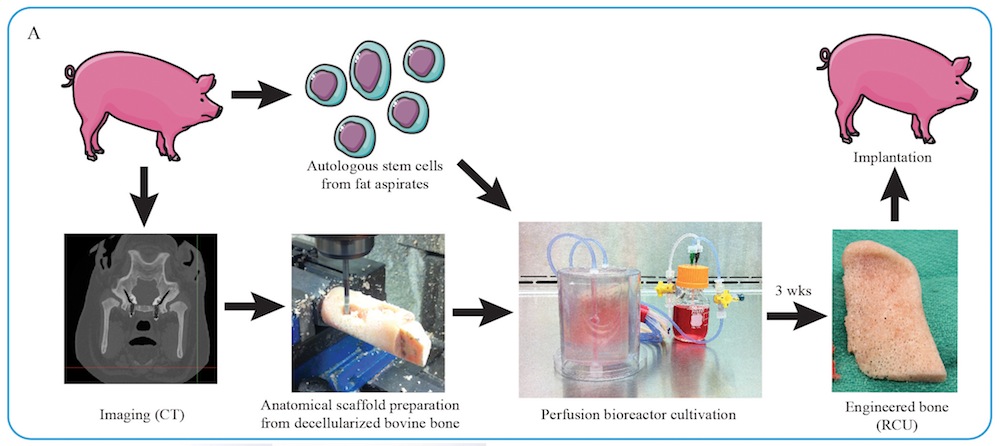

The investigator first take chunks of cow thighbones and divest them of all their cellular telephone using detergent and enzymes . They next carved these " decellularized " chunk into unadulterated anatomical fits for the ramus - condyle units that were surgically removed from the minipigs .

The scientists then seeded these off-white scaffolds withstem cellsderived from the fat of the minipigs that were to invite these transplant . The implant were then placed in " bioreactors " that cater the stem cellular telephone with atomic number 8 and nutrients .

After three weeks , the root word cells developed into immature livelihood ivory . " The pearl is formed by the recipient ’s own cells , " consider older generator Gordana Vunjak - Novakovic , a bioengineer at Columbia University , say Live Science .

A diagram of the personalized bone tissue engineering process. In the study, bone scaffolds were seeded with stem cells derived from the fat of minipigs.